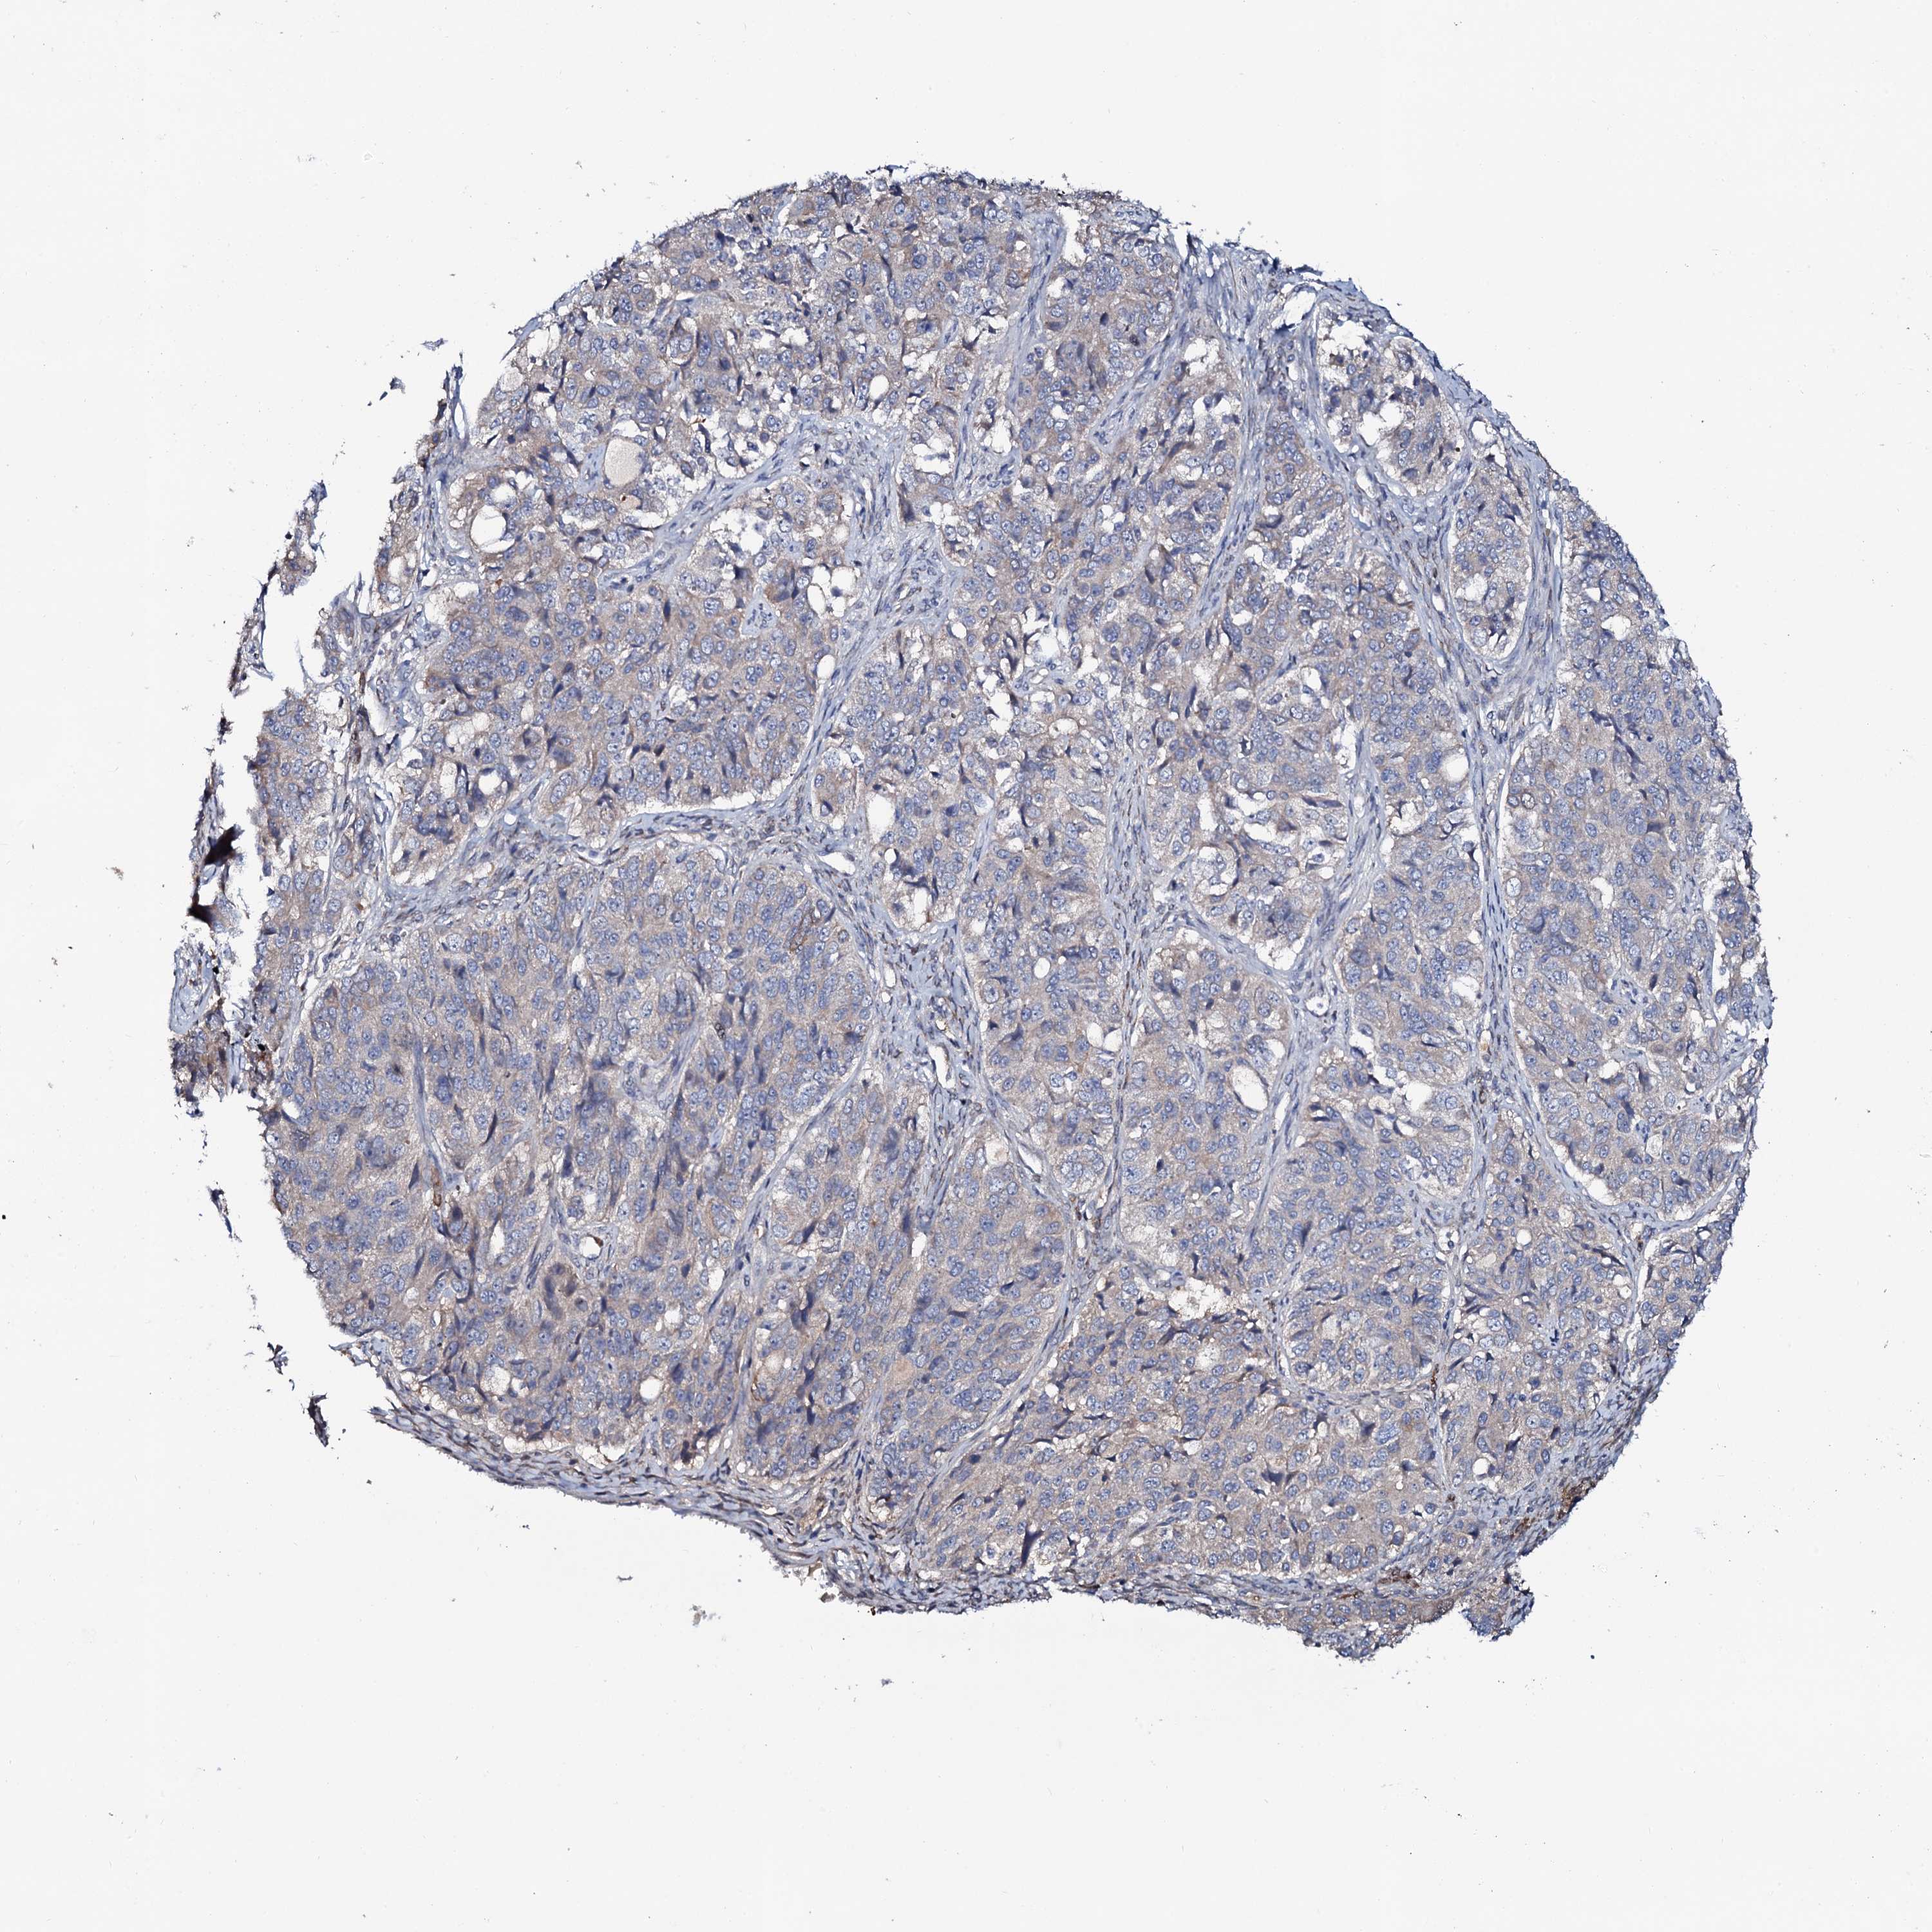

OVARIAN CANCER - Protein expressioni

A mouse-over function shows sample information and annotation data. Click on an image to view it in a full screen mode. Samples can be filtered based on level of antibody staining by selecting one or several of the following categories: high, medium, low and not detected. The assay and annotation is described here.

Note that samples used for immunohistochemistry by the Human Protein Atlas do not correspond to samples in the TCGA dataset.

Antibody stainingi

Antibody staining in the annotated cell types in the current human tissue is reported as not detected, low, medium, or high, based on conventional immunohistochemistry profiling in selected tissues. This score is based on the combination of the staining intensity and fraction of stained cells.

Each image is clickable and will lead to virtual microscopy that enables deeper exploration of all samples and also displays staining intensity scores, fraction scores and subcellular localization as well as patient and tissue information for each sample.

Antibody HPA041146

Cystadenocarcinoma, serous, NOS

Carcinoma, endometroid

Cystadenocarcinoma, mucinous, NOS

Carcinoma, NOS